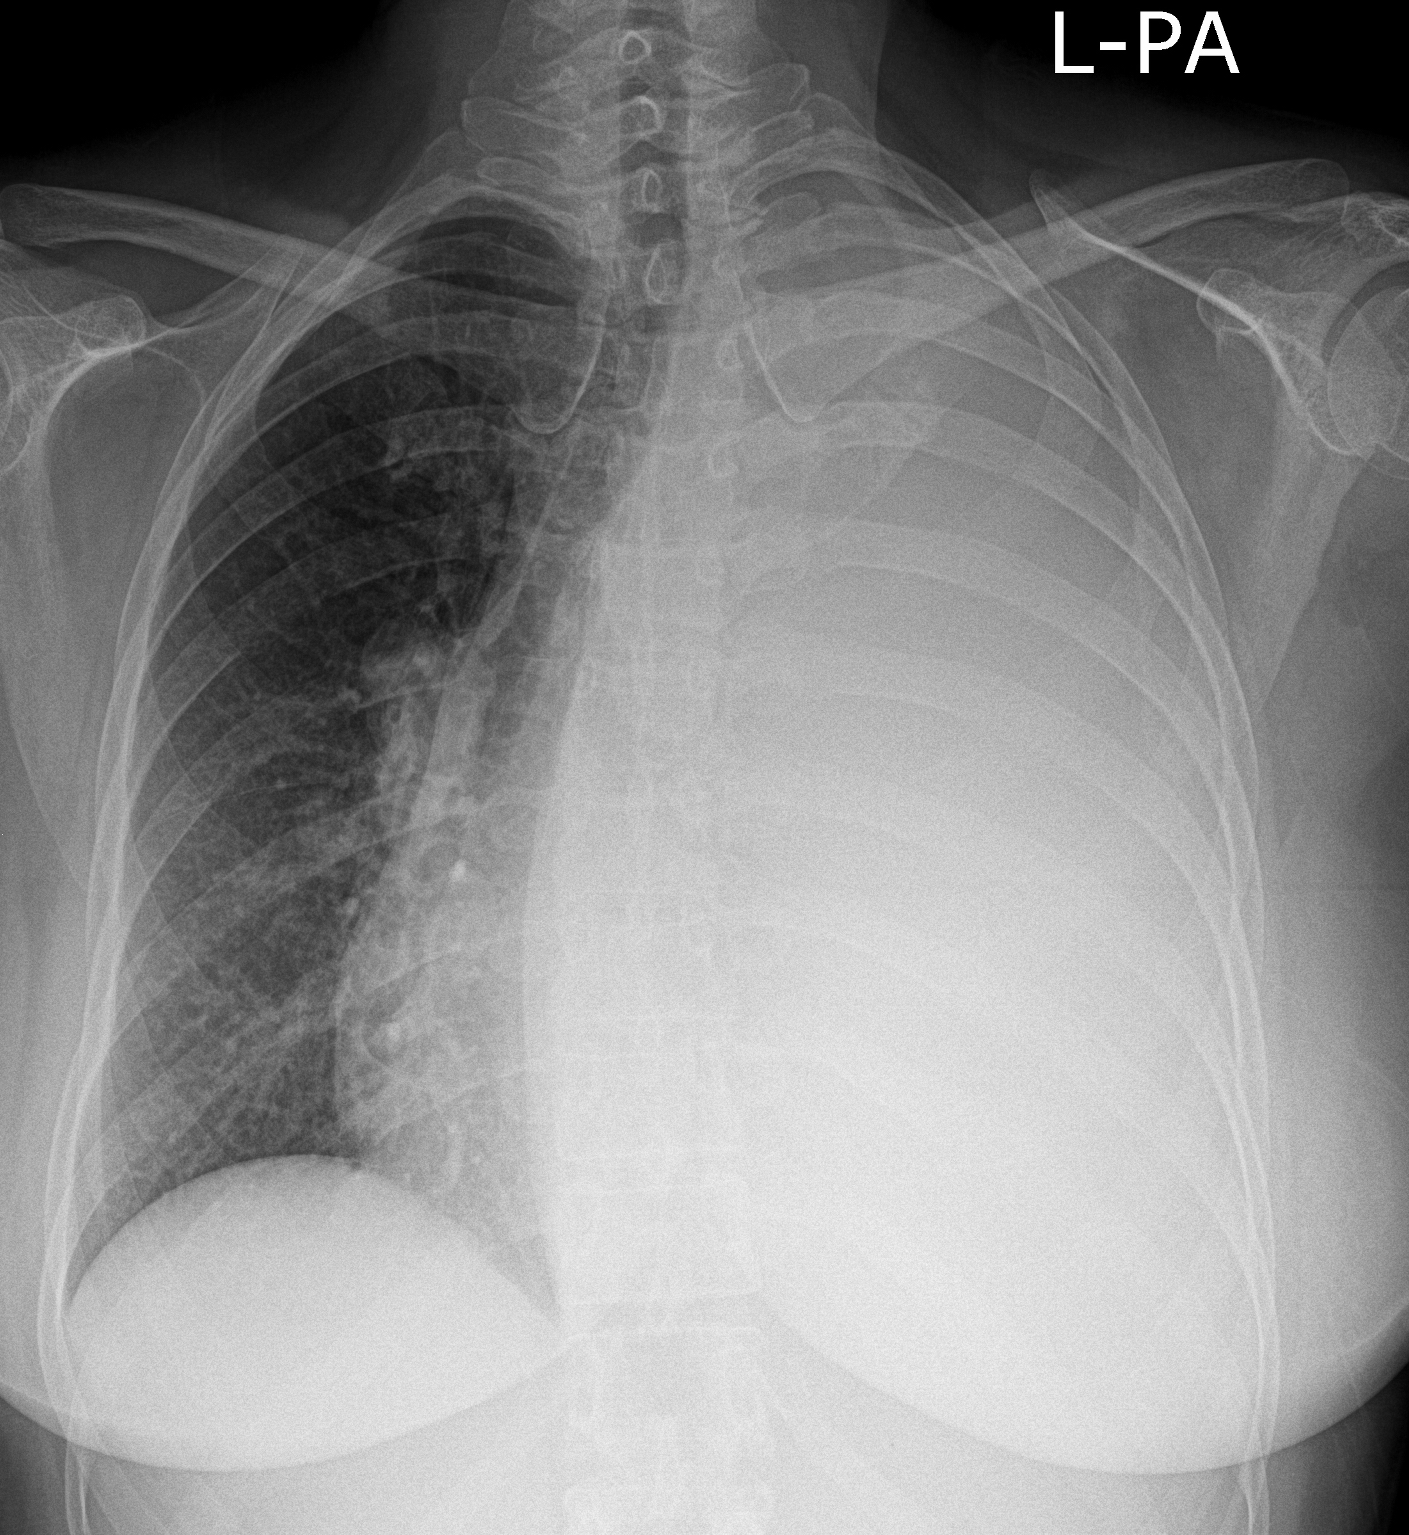

3a: Round shadow: multiple lung metastasis. Chest radiograph (PA)

Image

3b: Multiple lung metastasis, CT lung window (axial, coronal reformat)

3c, coronal reformat

70 year old man, colon tumor.

Radiograph: Bilateral extensive, confluating patchy-nodular shadowing with diffuse reticular pattern. The diaphragm contour is partially blurry bilaterally: lymphangiosis carcinomatosa.

CT: Numerous 1-6 cm round and irregular, lobulated-spiculated contrast enhancing lesions in both lungs, everywhere sporadically.